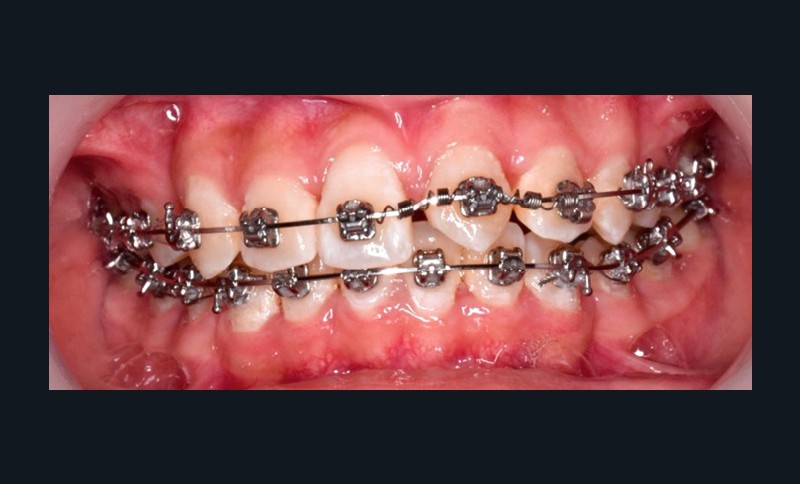

L’objectif du traitement est la correction de la DDA tout en assurant le remplacement de la 21 compromise. Décision a été prise d’extraire 34 et 44, ainsi que 21 et 14. La traction de la 23 a été réalisée à l’aide de forces légères, sur un arc transpalatin (fig. 9). Le nivellement et l’alignement, puis une mécanique par glissement ont permis d’aménager l’espace suffisant à la stratification de la canine. Elle associait un ressort en nickel-titane à des élastiques de Classe II (4 ½ oz, 3/16’’) sur un arc en acier .019×.025. Une phase d’ingression a été réalisée pour ajuster le niveau du bord libre de la canine à celui de l’incisive controlatérale (fig. 10-12).